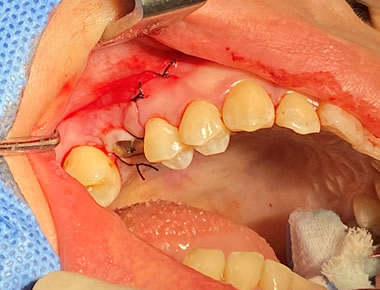

口蓋隆起 症例6(口蓋隆起形成術+親知らず抜歯)

無痛治療で口蓋隆起形成術。同時に左上の親知らずも抜歯しました。ピエゾサージェリーも使い低侵襲な手術を行いました。上顎の違和感がなくなります。

料金

静脈内鎮静法による麻酔代込み:約15万円(保険適用外)